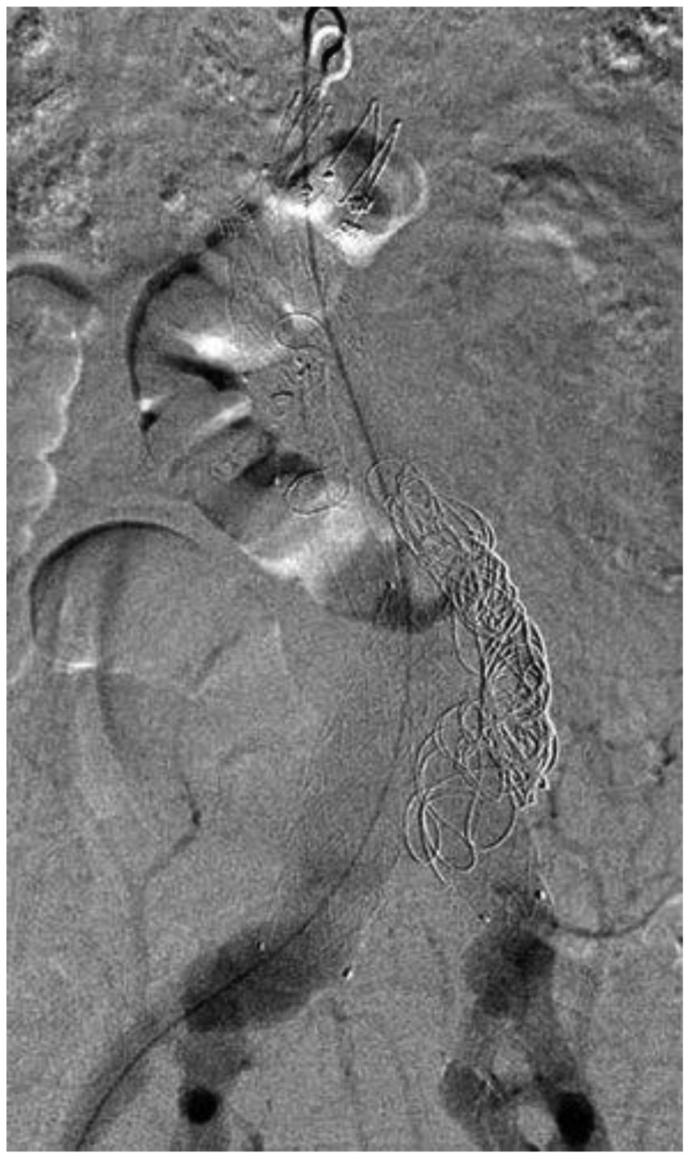

A primary aortocaval fistula (ACF) is a rare complication of abdominal aortic aneurysms caused by erosion of the aortic wall into the vena cava. It is more frequently observed in the setting of ruptured abdominal aortic aneurysms and presents a unique challenge for vascular surgeons. Both open and endovascular techniques exist, with the main differences being perioperative mortality and recurrence rates. We present a case of an ACF diagnosed intraoperatively, which persisted after endovascular aneurysm repair in conjunction with a type II endoleak. We applied a unique staged, triple endovascular approach to close the ACF via caval and aortic exclusion of inflow and outflow vessels.

原发性主动脉腔静脉瘘(ACF)是腹主动脉瘤的一种罕见并发症,由主动脉壁侵蚀进入腔静脉所致。在破裂性腹主动脉瘤中更常观察到,对血管外科医生构成独特挑战。开放手术和血管内技术都存在,主要区别在于围手术期死亡率和复发率。我们报告一例术中诊断为ACF的病例,该病例在血管内动脉瘤修复术后伴有II型内漏持续存在。我们采用了一种独特的分期、三重血管内方法,通过腔静脉和主动脉对流入和流出血管的封堵来闭合ACF。